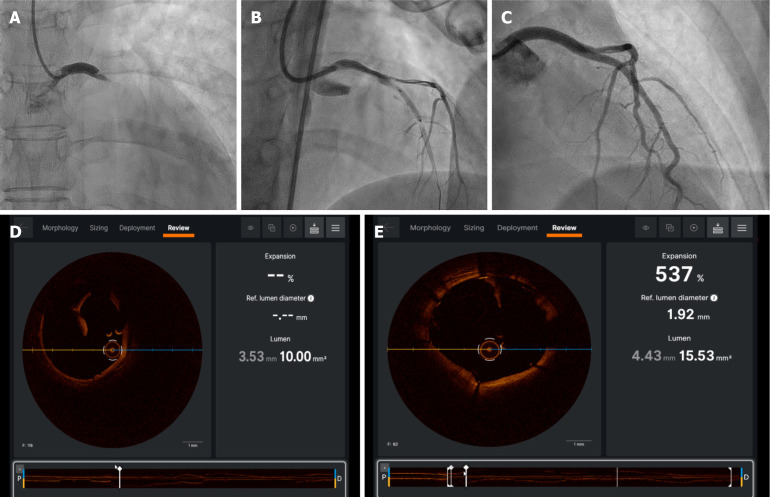

Abstract Image